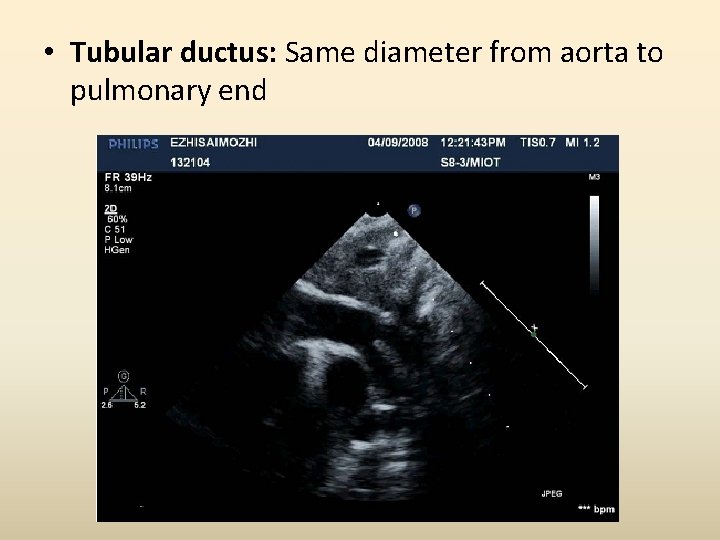

• Tubular ductus: Same diameter from aorta to pulmonary end